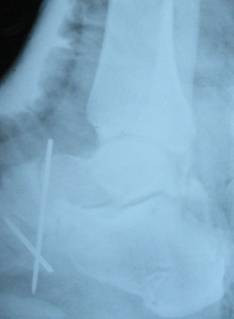

Figure 2.

Antero-posterior radiograph of the ankle showed total lateral talusr dislocation.